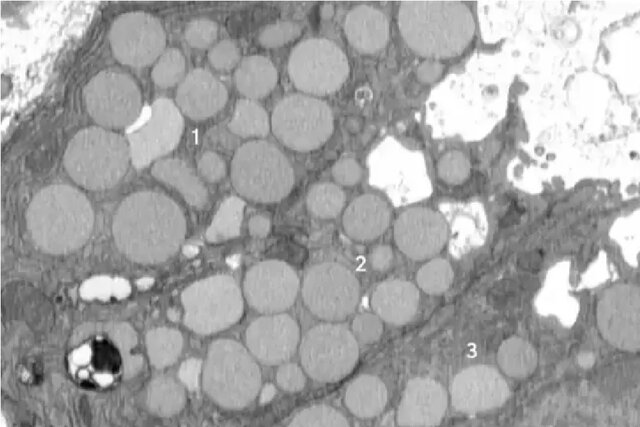

اساساً سلولها برای پاکسازی دستگاه سلولی خود، مواد زائد را استفراغ یا پاکسازی میکنند. این به عنوان یک میانبر عمل میکند که به آنها اجازه میدهد بافت سالم را سریعتر رشد دهند، زیرا روش معمول آنها برای تجزیه مواد زائد خیلی طول میکشد. با این حال، این عمل دارای معایبی است.

دکتر براون در طول تحقیقات مداوم خود متوجه وجود بقایایی در خارج از سلولها در یک مدل آسیب معده در موشها شد. او متوجه شد که با ادامه پخش شدن مواد زائد، اتفاقی عمدی در حال رخ دادن است. آسیب معده این اثر پاکسازی یا کاتارتوسیتوز را در پاسخ ترمیمی بزرگتر پالیژنوز ایجاد کرد. این زمانی است که یک سلول برای بهبودی به حالت سلول بنیادی برمیگردد.